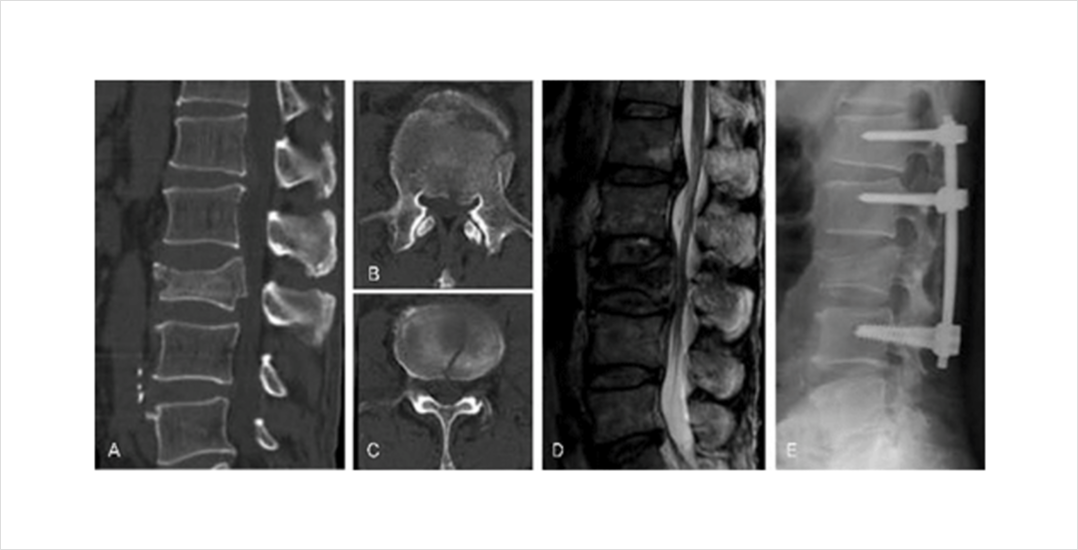

척추 골절이 심하여 골편이 신경을 압박하거나 골유합이 되지 않아 지속적인 불안정증이 있는 경우 척추체 고정술을 필요할 수 있습니다. 척추체 고정술이 필요한 경우에는 전문의와 자세한 상담이 필요합니다.

척추체 성형술을 시행하였지만 골시멘트와 유합이 일어나지 않고 척추체 내부에 괴사가 일어나면서 척추체의 붕괴가 진행되고 이로 인한 통증이 지속되는 경우도 있습니다. 이러한 경우에는 척추 불안정과 지속되는 통증을 해결하기 위해 척추체 고정술이 필요할 수 있습니다.